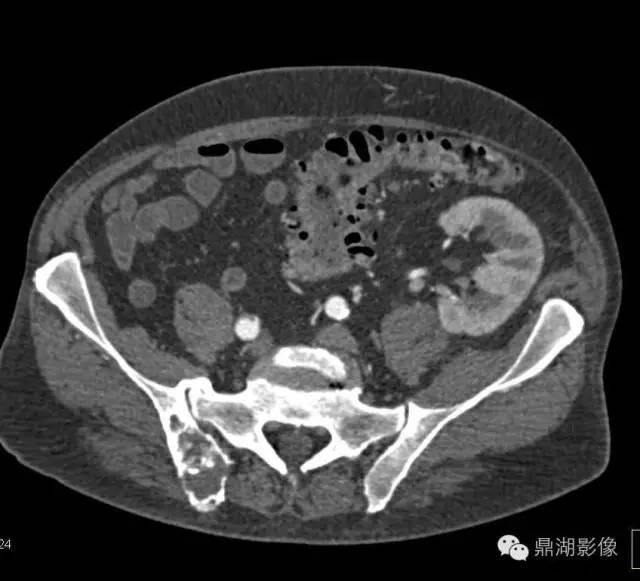

70岁,男,前列腺癌患者

(一)前列腺癌骨转移 前列腺癌发生骨转移的机会最多,占到所有男性骨转移的60%。国内有报道前列腺癌骨转移发生率50.9%,其中92.6%为成骨性改变,8.4%单纯溶骨性改变。转移部位以骨盆最多,其次腰椎、 胸椎、颈椎、股骨粗隆、肋骨、胸骨,年龄多在60岁以上。

X线片表现:成骨性转移表现为在骨外型没有改变的骨背景上出现圆形或椭圆形致密影,有时呈地图状,边缘不规则,多数病灶可融合成片,也有病灶累及大部分或整个骨,有时在成骨性病灶边缘散在少量溶骨性破坏。密度呈棉絮样增高。前列腺癌骨转移多较典型,结合临床,诊断一般不难。

实验室检查,血清碱性磷酸酶常增高,约占80%~85%;血清酸性磷酸酶也明显增高,对诊断前列腺癌骨转移有重要价值。